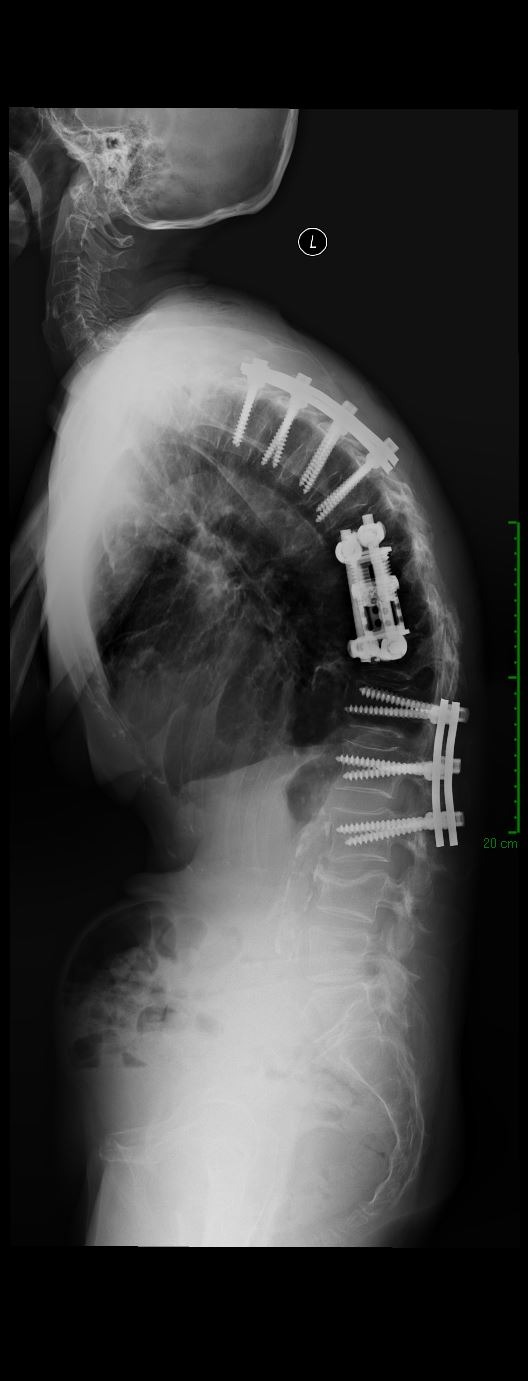

De-identified imaging from complex spine surgery cases. Each pair shows pre-operative pathology alongside post-operative correction across cervical, lumbar and deformity subspecialties.